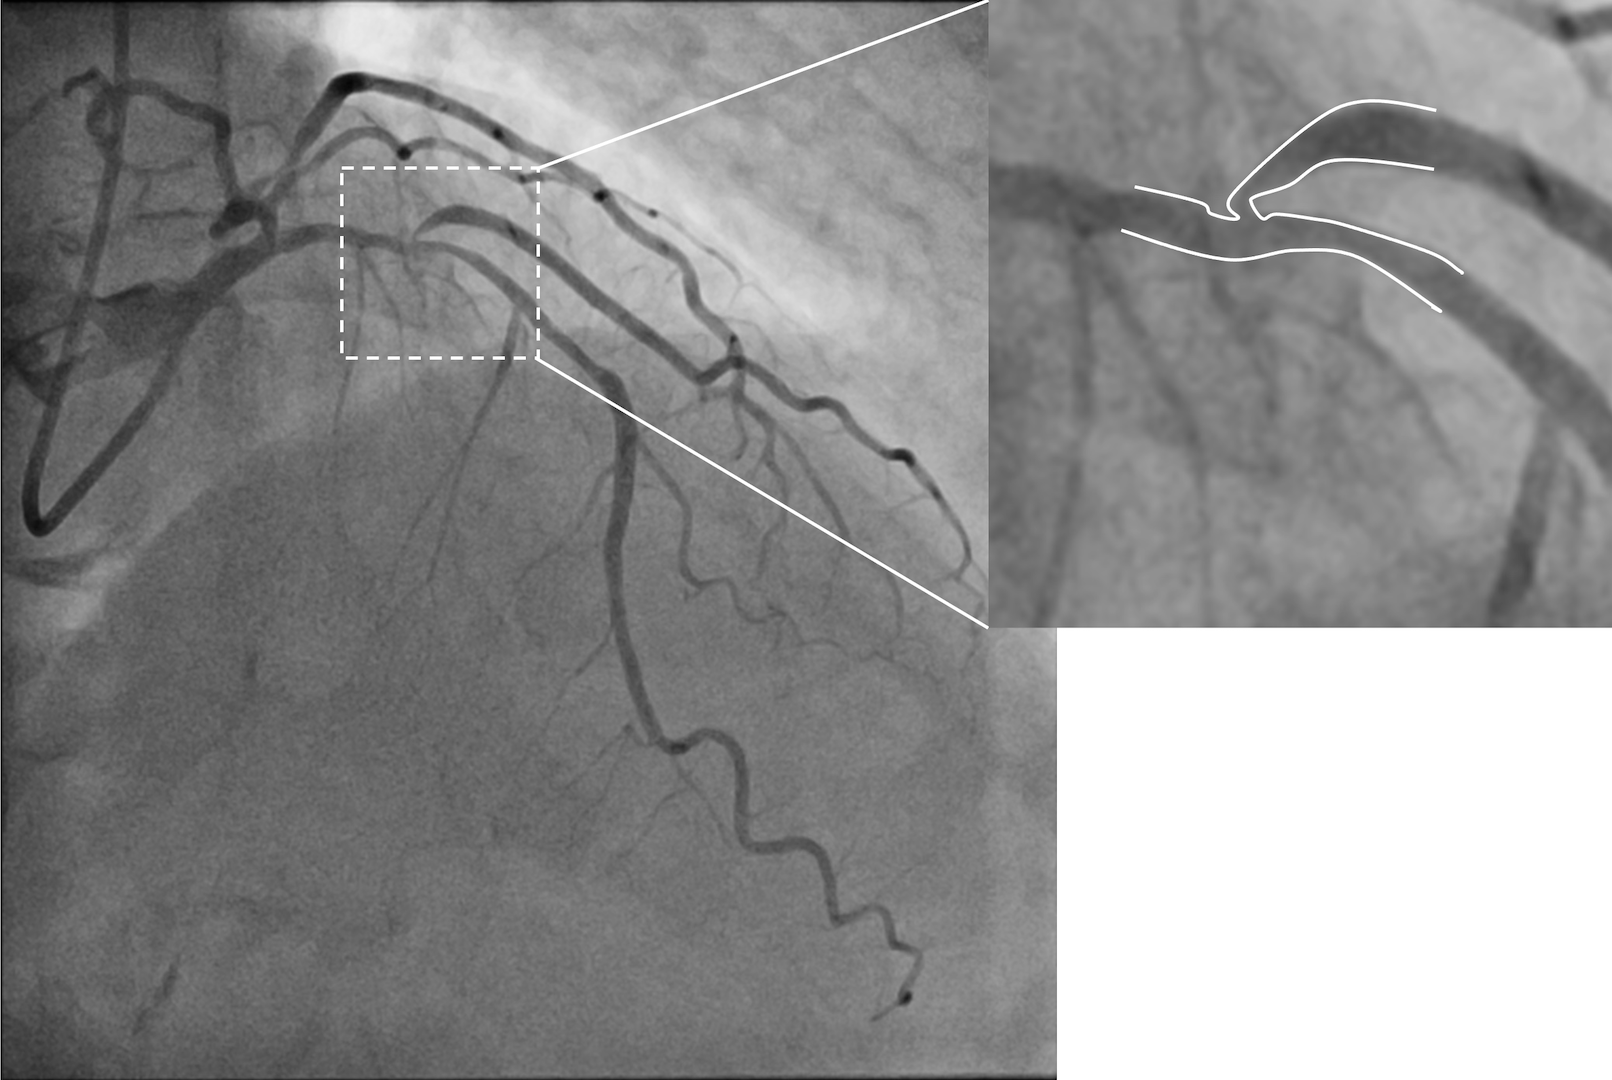

A 75-year-old man was admitted for non-ST-segment elevation myocardial infarction (NSTEMI). Coronary angiography showed focal severe disease at obtuse marginal artery (OM) and severe medina 1,1,1 bifurcation disease involving proximal to middle left anterior descending artery (LAD) and a sizable diagonal branch (Figure 1A, Video 1). With a 6-French extra backup (EBU) 3.5 guide catheter, the LAD was wired with a workhorse guidewire. The diagonal branch had a retroflex takeoff and initial wiring was subintimal (Figure 1B). Parallel wire technique (PWT) with Gaia Next 1 (Asahi Intecc) successfully rewired the true lumen and steered into the distal part of the diagonal branch (Figure 1C, D; Video 2). The LAD was provisionally stented with the diagonal branch protected by jailed balloon technique (JBT) of a 2.0 mm semi-compliant balloon, followed by stenting of the OM (Figure 1E). The final angiographic results were good (Figure 1F, Video 3).

Wiring of an extremely angulated side branch (SB) is challenging. Classic techniques include reverse wire technique (RWT) and the use of specialized microcatheters. Yet the delivery of these systems usually requires prior lesion preparation, running the risk of plaque or carina shift that can further jeopardize the SB. Our case highlighted several strengths of using chronic total occlusion (CTO) wiring techniques in overcoming such complicated anatomy: (1) PWT allows straightening of the SB angulation; (2) the Gaia family of CTO wires possesses excellent steerability permitting active wire control for negotiation despite in extreme angulation,; (3) no lesion preparation is required that may compromise SB access; and (4) only ordinary microcatheters are required, which are widely available and allow easy modification and exchange of guidewires. The Gaia Next 1 wire used in this case has a pre-shaped distal curve. We suggest shaping an additional 30° to 40° secondary curve matched with vessel size to help with SB access.